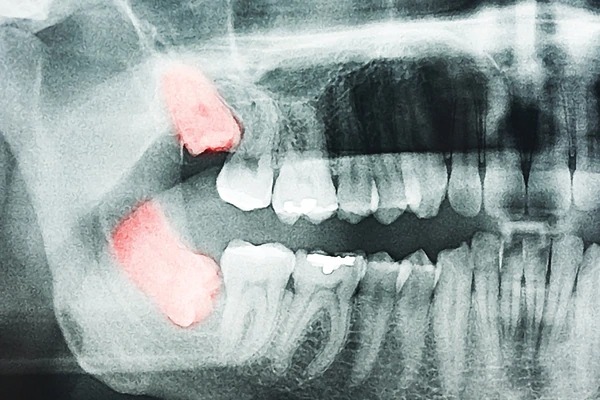

La doctora afirma que los rostros se están volviendo mucho más cortos, con mandíbulas pequeñas, dejando menos espacio para los dientes. Esto ha ido sucediendo con el tiempo, ya que hemos aprendido a utilizar el fuego y a procesar los alimentos antes de ingerirlos.

En particular, cada vez son más los niños nacen sin muelas del juicio.

“Esto está sucediendo con el tiempo, ya que hemos aprendido a utilizar más el fuego y a procesar los alimentos. Mucha gente está naciendo sin muelas del juicio”, indica textualmente la doctora Lucas.